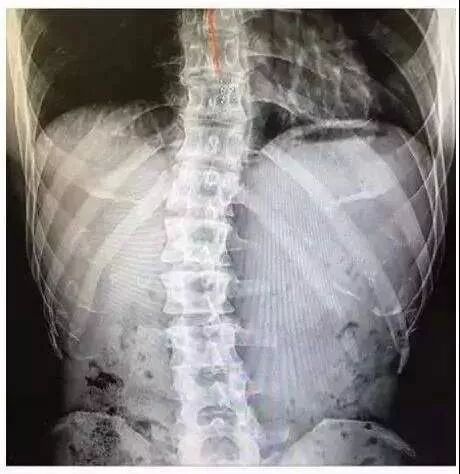

我本身是脊柱侧弯

而后引发了强直性脊柱炎

(这个病是必须遗传的)

于是在一个应该能跑能跳的年纪

MAX的髋关节已经被侵蚀腐坏

脊柱也是大面积形变侧弯